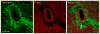

In mice and humans, loss of myosin VI (Myo6) function results in deafness, and certain Myo6 mutations also result in cardiomyopathies in humans. The current studies have utilized the Snell's waltzer (sv) mouse (a functional null mutation for Myo6) to determine if this mouse also exhibits cardiac defects and thus used to determine the cellular and molecular basis for Myo6-associated heart disease. Myo6 is expressed in mouse heart where it is predominantly expressed in vascular endothelial cells (VECs) based on co-localization with the VEC cell marker CD31. Sv/sv heart mass is significantly greater than that of sv/+ littermates, a result of left ventricle hypertrophy. The left ventricle of the sv/sv exhibits extensive fibrosis, both interstitial and perivascular, based on histologic staining, and immunolocalization of several markers for fibrosis including fibronectin, collagen IV, and the fibroblast marker vimentin. Myo6 is also expressed in lung VECs but not in VECs of intestine, kidney, or liver. Sv/sv lungs exhibit increased periaveolar fibrosis and enlarged air sacs. Electron microscopy of sv/sv cardiac and lung VECs revealed abnormal ultrastructure, including luminal protrusions and increased numbers of cytoplasmic vesicles. Previous studies have shown that loss of function of either Myo6 or its adaptor binding partner synectin/GIPC results in impaired arterial development due to defects in VEGF signaling. However, examination of synectin/GIPC-/- heart revealed no fibrosis or significantly altered VEC ultrastructure, suggesting that the cardiac and lung defects observed in the sv/sv mouse are not due to Myo6 function in arterial development.